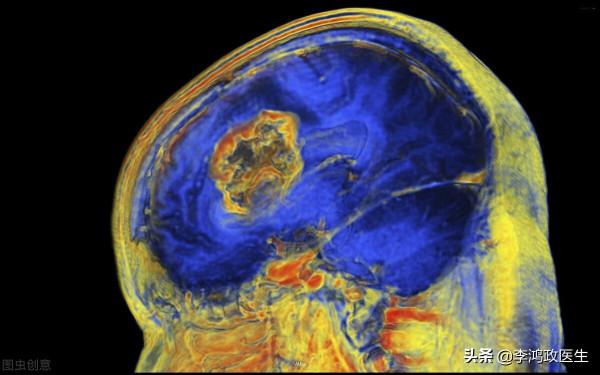

這回看的更清楚了,影像科醫生和神經內科、神經外科醫生坐在了一起,討論了,認為左側顳葉這個東西是個膠質瘤。

膠質瘤是大腦最常見的惡性腫瘤,但惡性程度也分高低,有些人的很兇險,有些人的比較緩和,得看情況,從目前的影像學來看,可能是個偏惡性的。醫生給出了答覆。

醫生說了,對付膠質瘤,手術是肯定的,你之前頭痛、暈倒等等,都可能是膠質瘤引起的,膠質瘤可能導致顱內高壓,也可能直接侵襲相關腦神經,引發一系列問題。手術切掉是最靠譜的。至於要不要放療和化療,就看術後情況了。多數人是需要的。